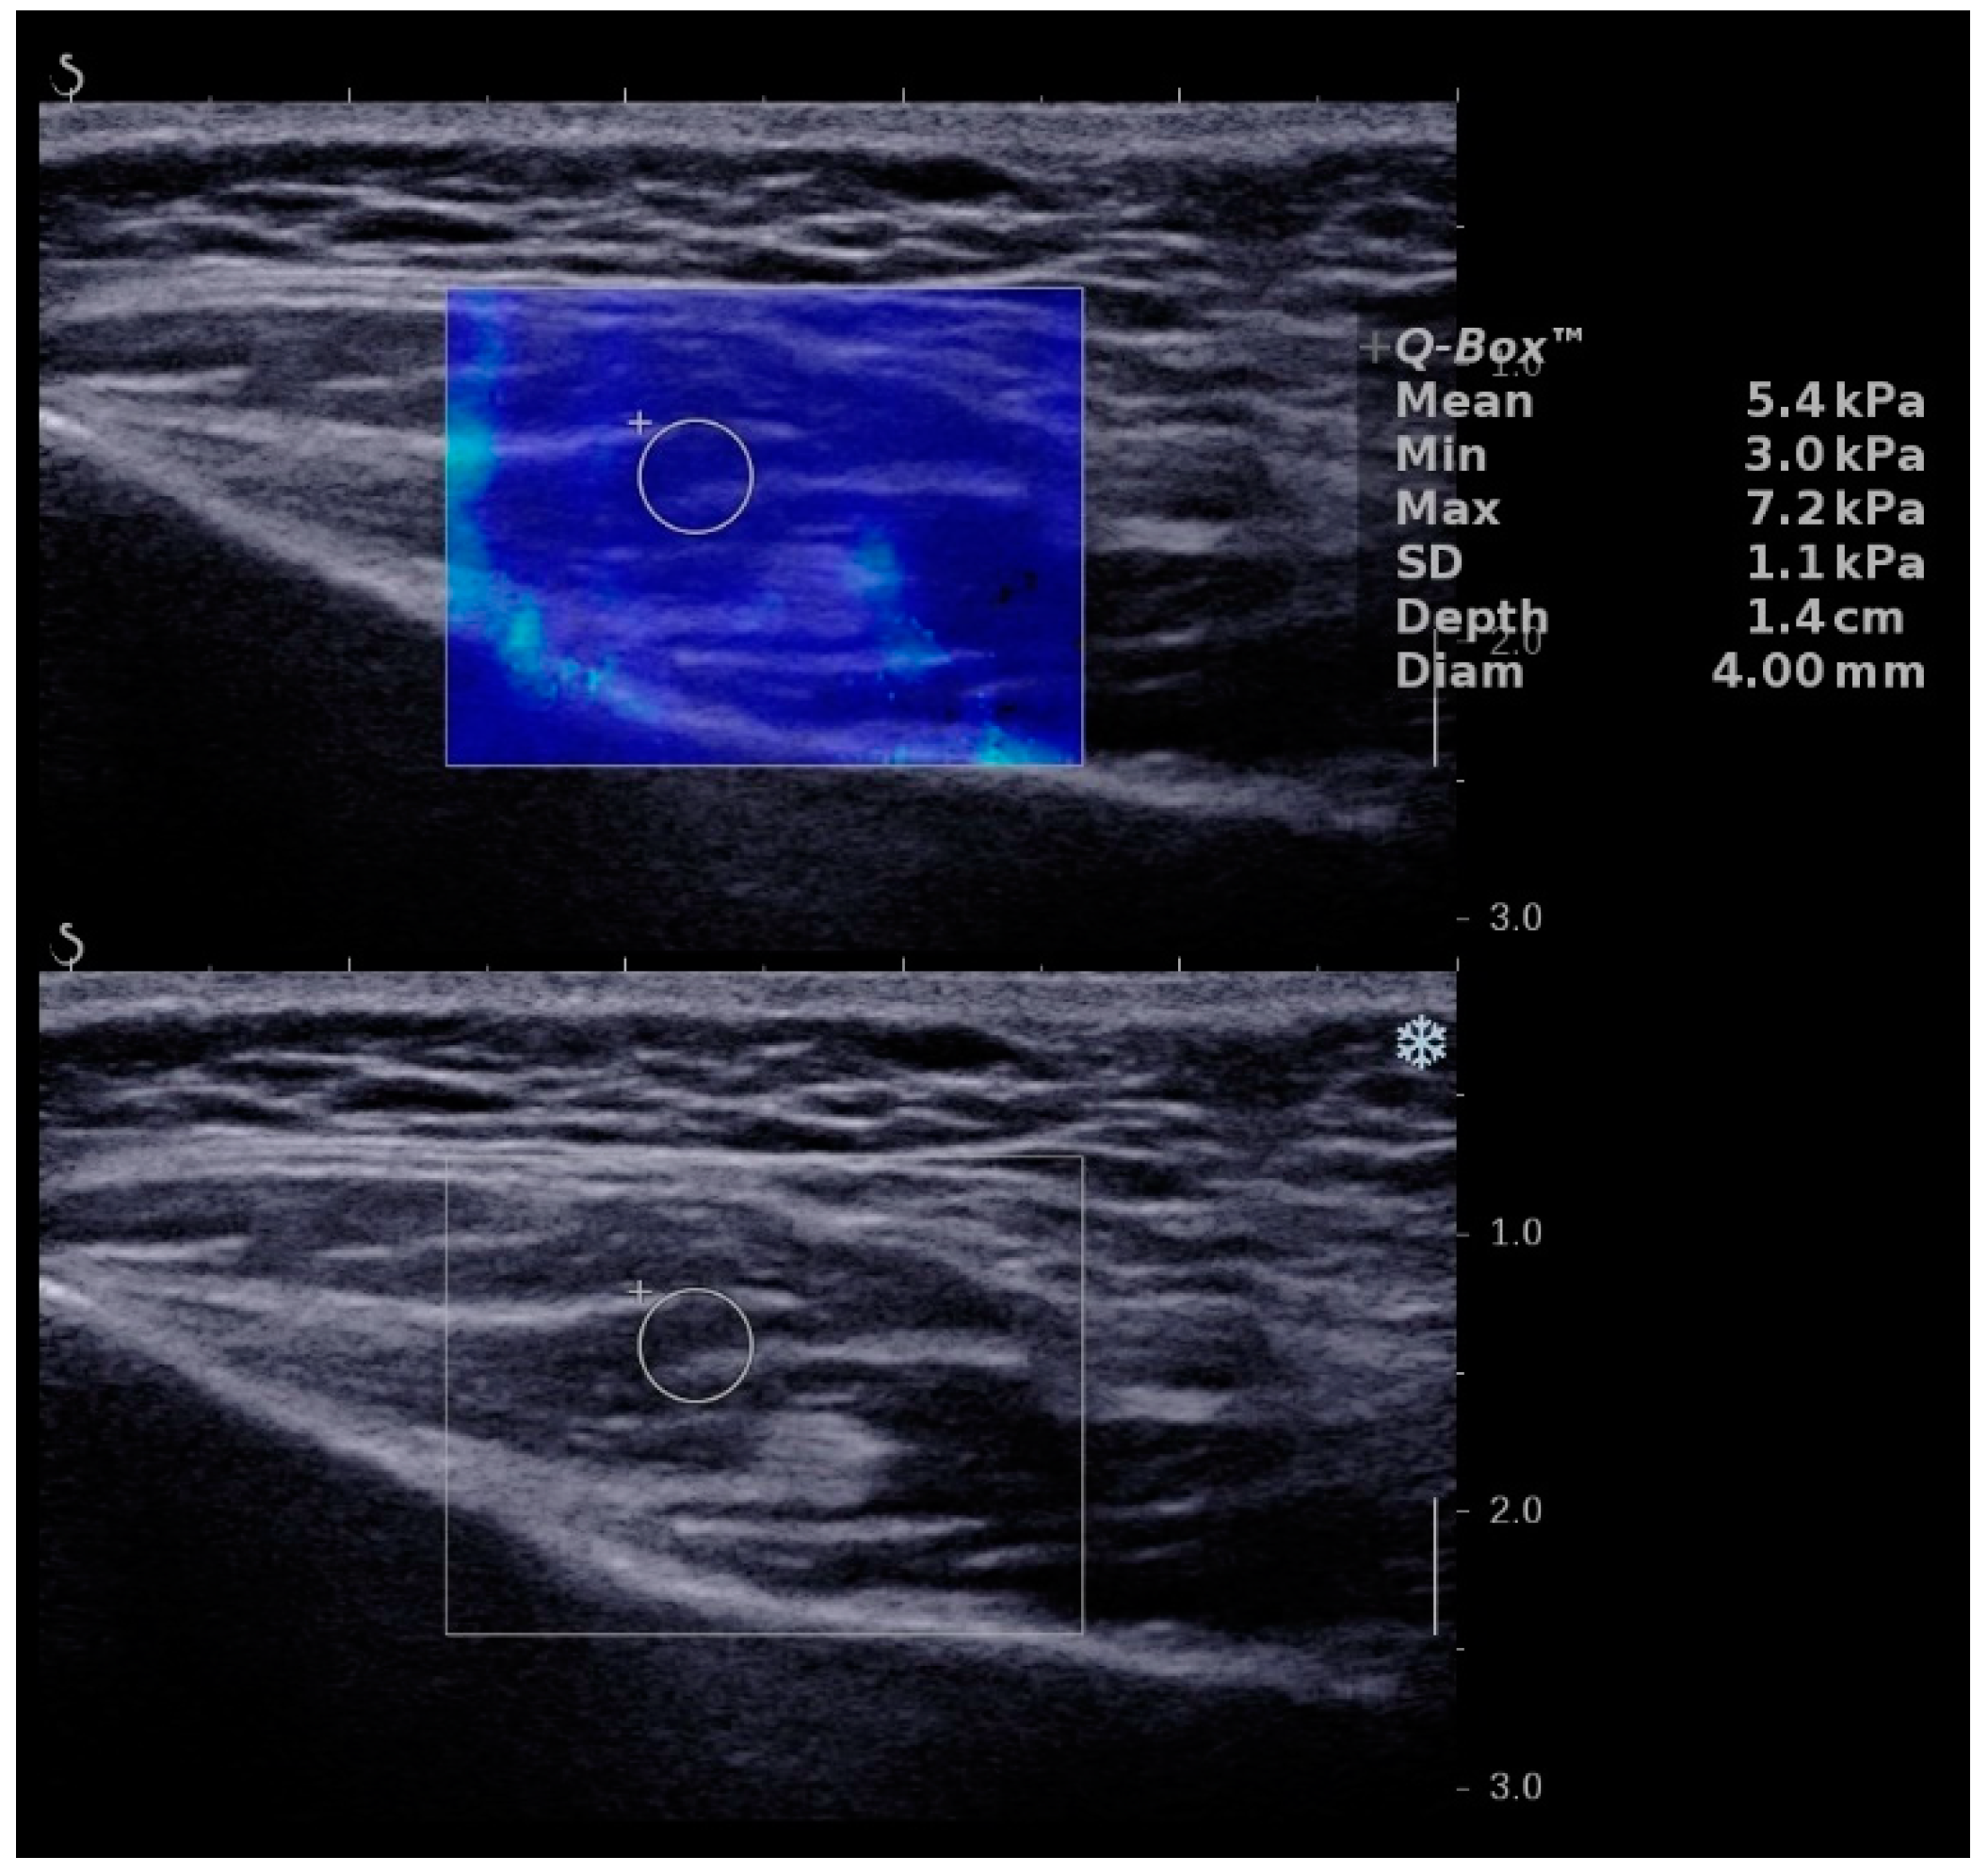

| Group | Mean ± SD | Median (IQR) |

|---|---|---|

| Total | ||

| Age (year) | 10.87 ± 3.38 | 12.00 (9.25–13.00) |

| Left masseter (kPa) | 6.47 ± 0.78 | 6.33 (6.11–7.04) |

| SD of left masseter | 1.45 ± 0.42 | 1.41 (1.11–1.63) |

| Right masseter (kPa) | 6.24 ± 0.76 | 6.30 (5.58–6.71) |

| SD of right masseter | 1.41 ± 0.52 | 1.40 (0.91–1.83) |

| Girls | ||

| Age (year) | 10.28 ± 4.16 | 11.50 (8.25–13.00) |

| Total value (kPa) | 6.63 ± 0.80 | 6.68 (6.10–7.13) |

| Left masseter (kPa) | 6.72 ± 0.85 | 6.87 (6.17–7.13) |

| SD of left masseter | 1.62 ± 0.42 | 1.60 (1.37–1.70) |

| Right masseter (kPa) | 6.54 ± 0.77 | 6.63 (5.87–6.77) |

| SD of right masseter | 1.61 ± 0.53 | 1.73 (1.00–2.03) |

| Boys | ||

| Age (year) | 11.75 ± 1.42 | 12.00 (11.00–13.00) |

| Total value (kPa) | 5.94 ± 0.50 | 6.12 (5.55–6.30) |

| Left masseter (kPa) | 6.09 ± 0.46 | 6.17 (6.10–6.31) |

| SD of left masseter | 1.20 ± 0.30 | 1.12 (1.06–1.31) |

| Right masseter (kPa) | 5.80 ± 0.52 | 5.67 (5.50–6.30) |

| SD of right masseter | 1.10 ± 0.33 | 0.92 (0.86–1.40) |